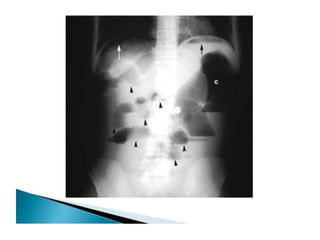

• 32.

OTHER SIGNS- • Conicalcaecum- shrunken in size and pulled out of the iliac fossa due to contraction and fibrosis of the mesocolon. The hepatic flexure may also be pulled down. • Early involvement of the ileocaecal region manifesting as spasm and oedema of the ileocaecal valve. Thickening of the lips of the ileocaecal valve and/or wide gaping of the valve with narrowing of the terminal ileum (“Fleischner” or “inverted umbrella sign”) are characteristic.

• 33.

• “String sign”– persistant narrow stream of barium indicating stenosis. • Purse string stenosis– localized stenosis opposite the ileocaecal valve with a rounded off smooth caecum and a dilated terminal ileum.